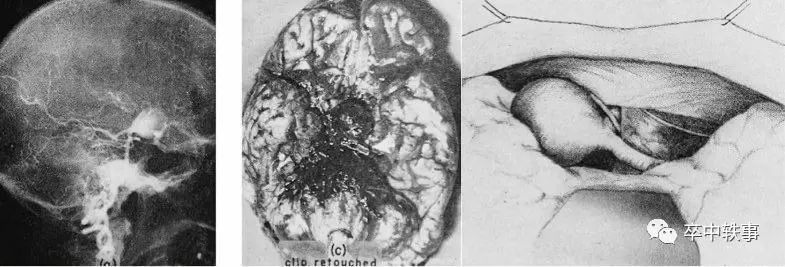

后循环(上图左)动脉瘤手术难做,一是位置深,入路难;二是紧贴脑干和小脑,风险大;三是病人少,多数神外医生没有后循环动脉瘤手术的经验。

这四例报道建立了基底动脉瘤的标准入路,同时创新的加入低温,腰穿引流,局部脑循环暂停等技术,并且指出脑血管痉挛的可能后果。

Drake 的研究引起人们观注脑动脉瘤和蛛网膜下腔出血,尤其是脑血管痉挛,以及术后造影的重要性和术中人为低血压的安全和局限性。

因为与神经放射医生的合作,Drake 在1965年即认识到脑血管痉挛的重要性,他发表了:“动脉瘤破裂后,脑血管痉挛的意义 - Allcook JM, Drake CG. Ruptured Intracranial Aneurysms - the Role of Arterial Spasm. J Neurosurg 22: 21-29, 1965”。

为了做复杂的基底动脉瘤手术,Drake 使用人工低温和短时停止心脏循环,需要強大的麻醉团队。Drake 报道了他的经验:“治疗后循环动脉瘤 - Drake CG. The Treatment of Aneurysms of the Posterior Circulation. Clin Neurosurg 26: 96-144, 1979(上图)”。

在1958年 Drake 开创了从颞前上方入颅夹闭基底动脉瘤的手术入路。